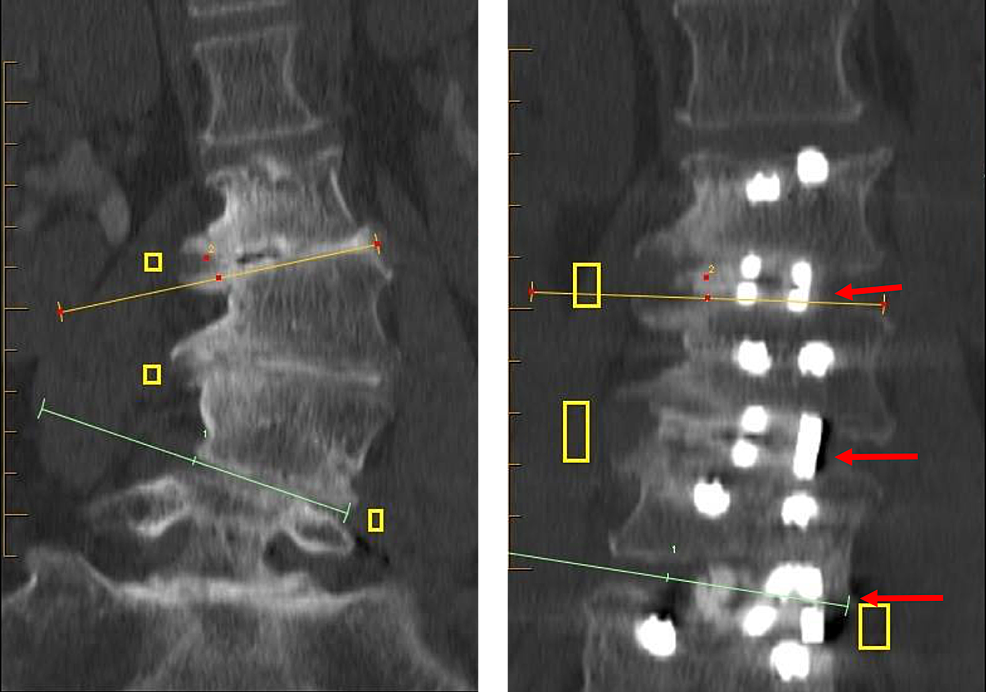

Other than the above considerations, the technical approach to discectomy, endplate preparation, and cage entry are as described in our OLLIF technical paper [14]. The correction of deformity is achieved through careful cage placement: right and left for lateral scoliosis correction and anterior and posterior for lordosis correction. To enable a more horizontal cage placement, the OLLIF approach can be modified to enter the disc space anterior to the nerve root rather than through the Kambin’s triangle, similarly to MIS-DLIF [16]. Some electrophysiological activity is not unusual during cage entry. However, all activity subsides after the cage is placed because the cage increases pedicle distance and causes anatomical/physiological foraminotomy (indirect decompression). A fluoroscopic image of completed cage entry is then taken to confirm positioning. Imaging illustrating the cage after a completed procedure is shown in Figure 3.